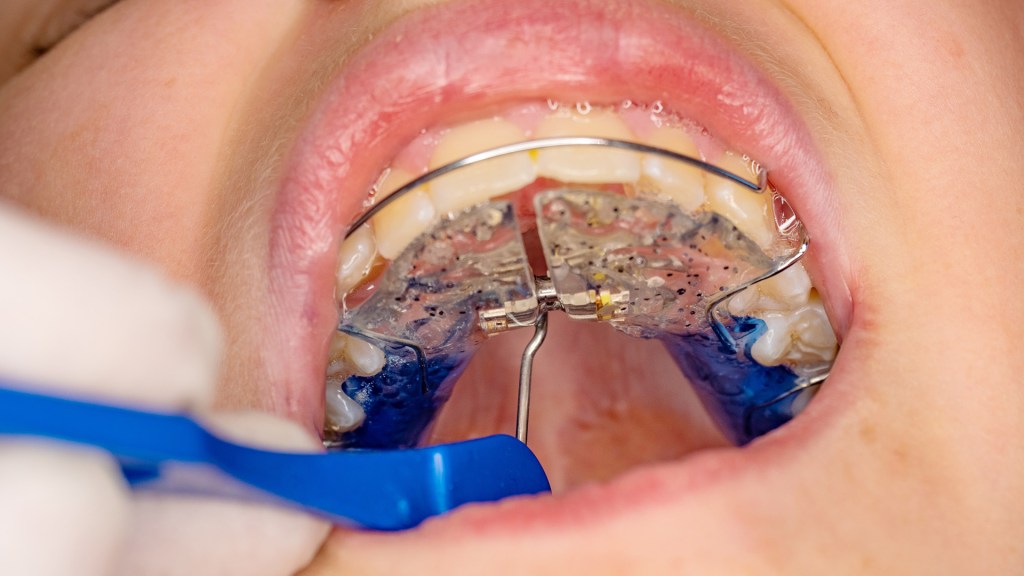

Os dispositivos mais utilizados incluem expansores do tipo Hyrax, Haas e suas variações contemporâneas, além de aparelhos assistidos por mini-implantes.

A instalação deve garantir estabilidade, adaptação passiva inicial e correta distribuição das forças.

Uma instalação inadequada compromete tanto a eficiência da expansão quanto o conforto do paciente, além de aumentar o risco de efeitos colaterais.